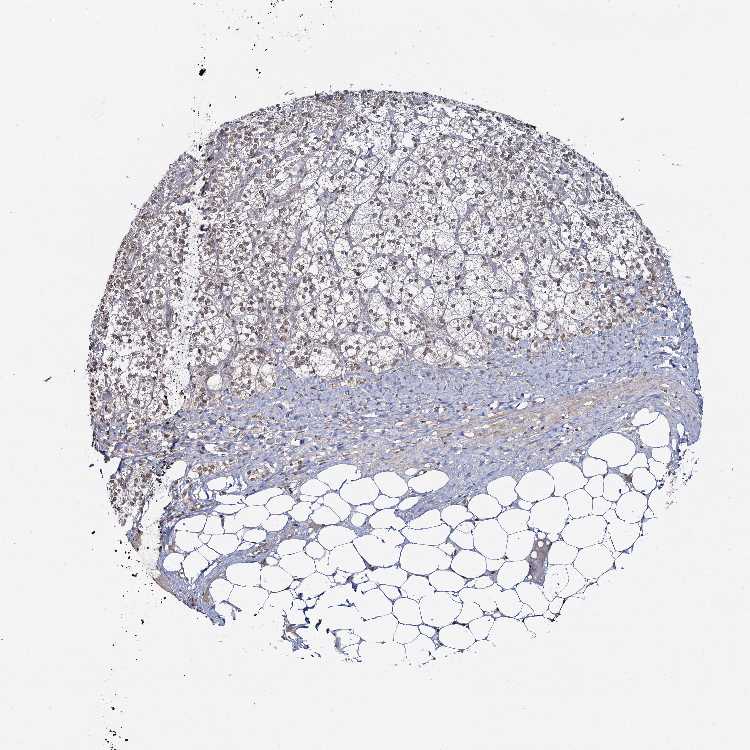

ADRENAL GLAND - Antibody stainingi

Antibody staining in the annotated cell types in the current human tissue is reported as not detected, low, medium, or high, based on conventional immunohistochemistry profiling in selected tissues. This score is based on the combination of the staining intensity and fraction of stained cells.

Each image is clickable and will lead to virtual microscopy that enables deeper exploration of all samples and also displays staining intensity scores, fraction scores and subcellular localization as well as patient and tissue information for each sample.

Antibody HPA039343Antibody HPA040048

Glandular cells LowHigh